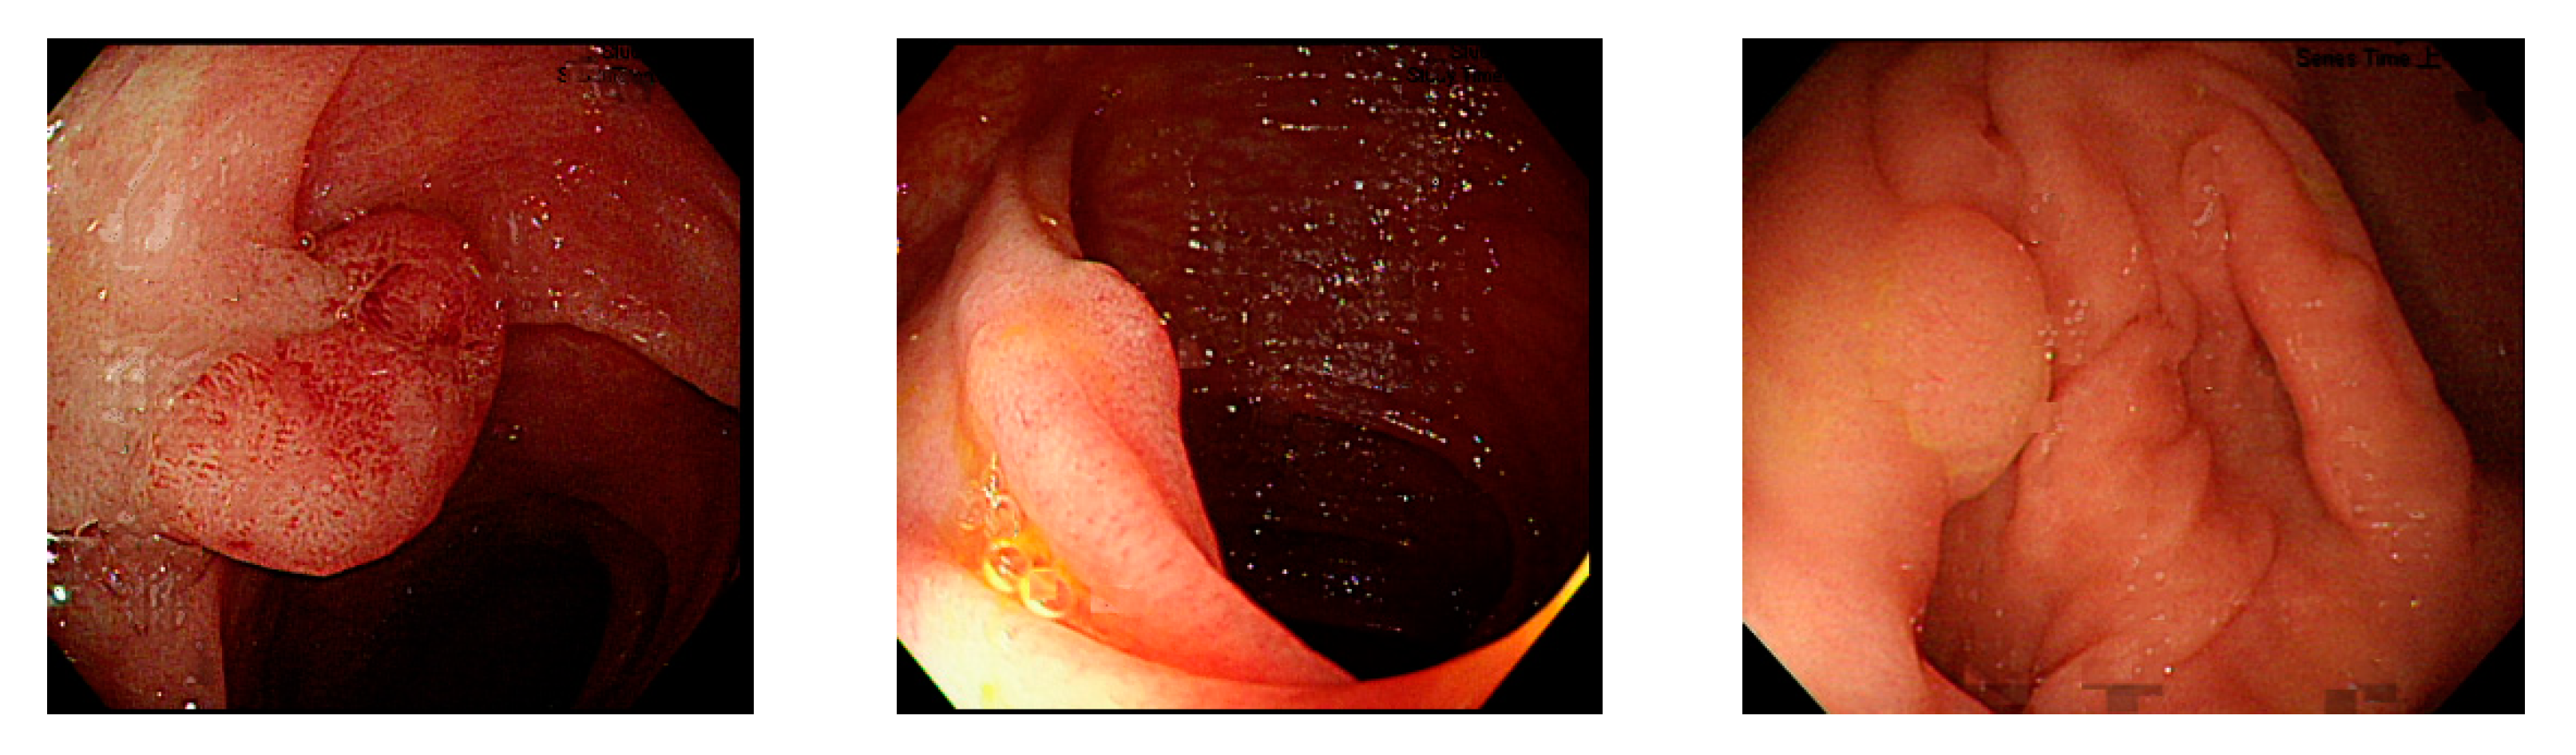

In polyp classification, neoplastic polyps were likely to be misjudged as hyperplastic polyps when polyp textures were not obvious (Figure 16), images had an excessively low resolution, or when polyps were smaller than 1800 pixels (Figure 17). Hyperplastic polyps, however, were likely to be misjudged as neoplastic polyps because of the WL around polyps in the images and when polyps were smaller than 1800 pixels.

Figure 16.

Unobvious polyp textures.

Figure 17.

Polyp image size below 1800 pixels.